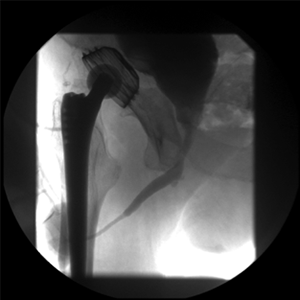

Vor der OP

Nach der OP

mit Mundschleimhauttransplantation

Mundschleimhaut-onlay (buccal mucosa)